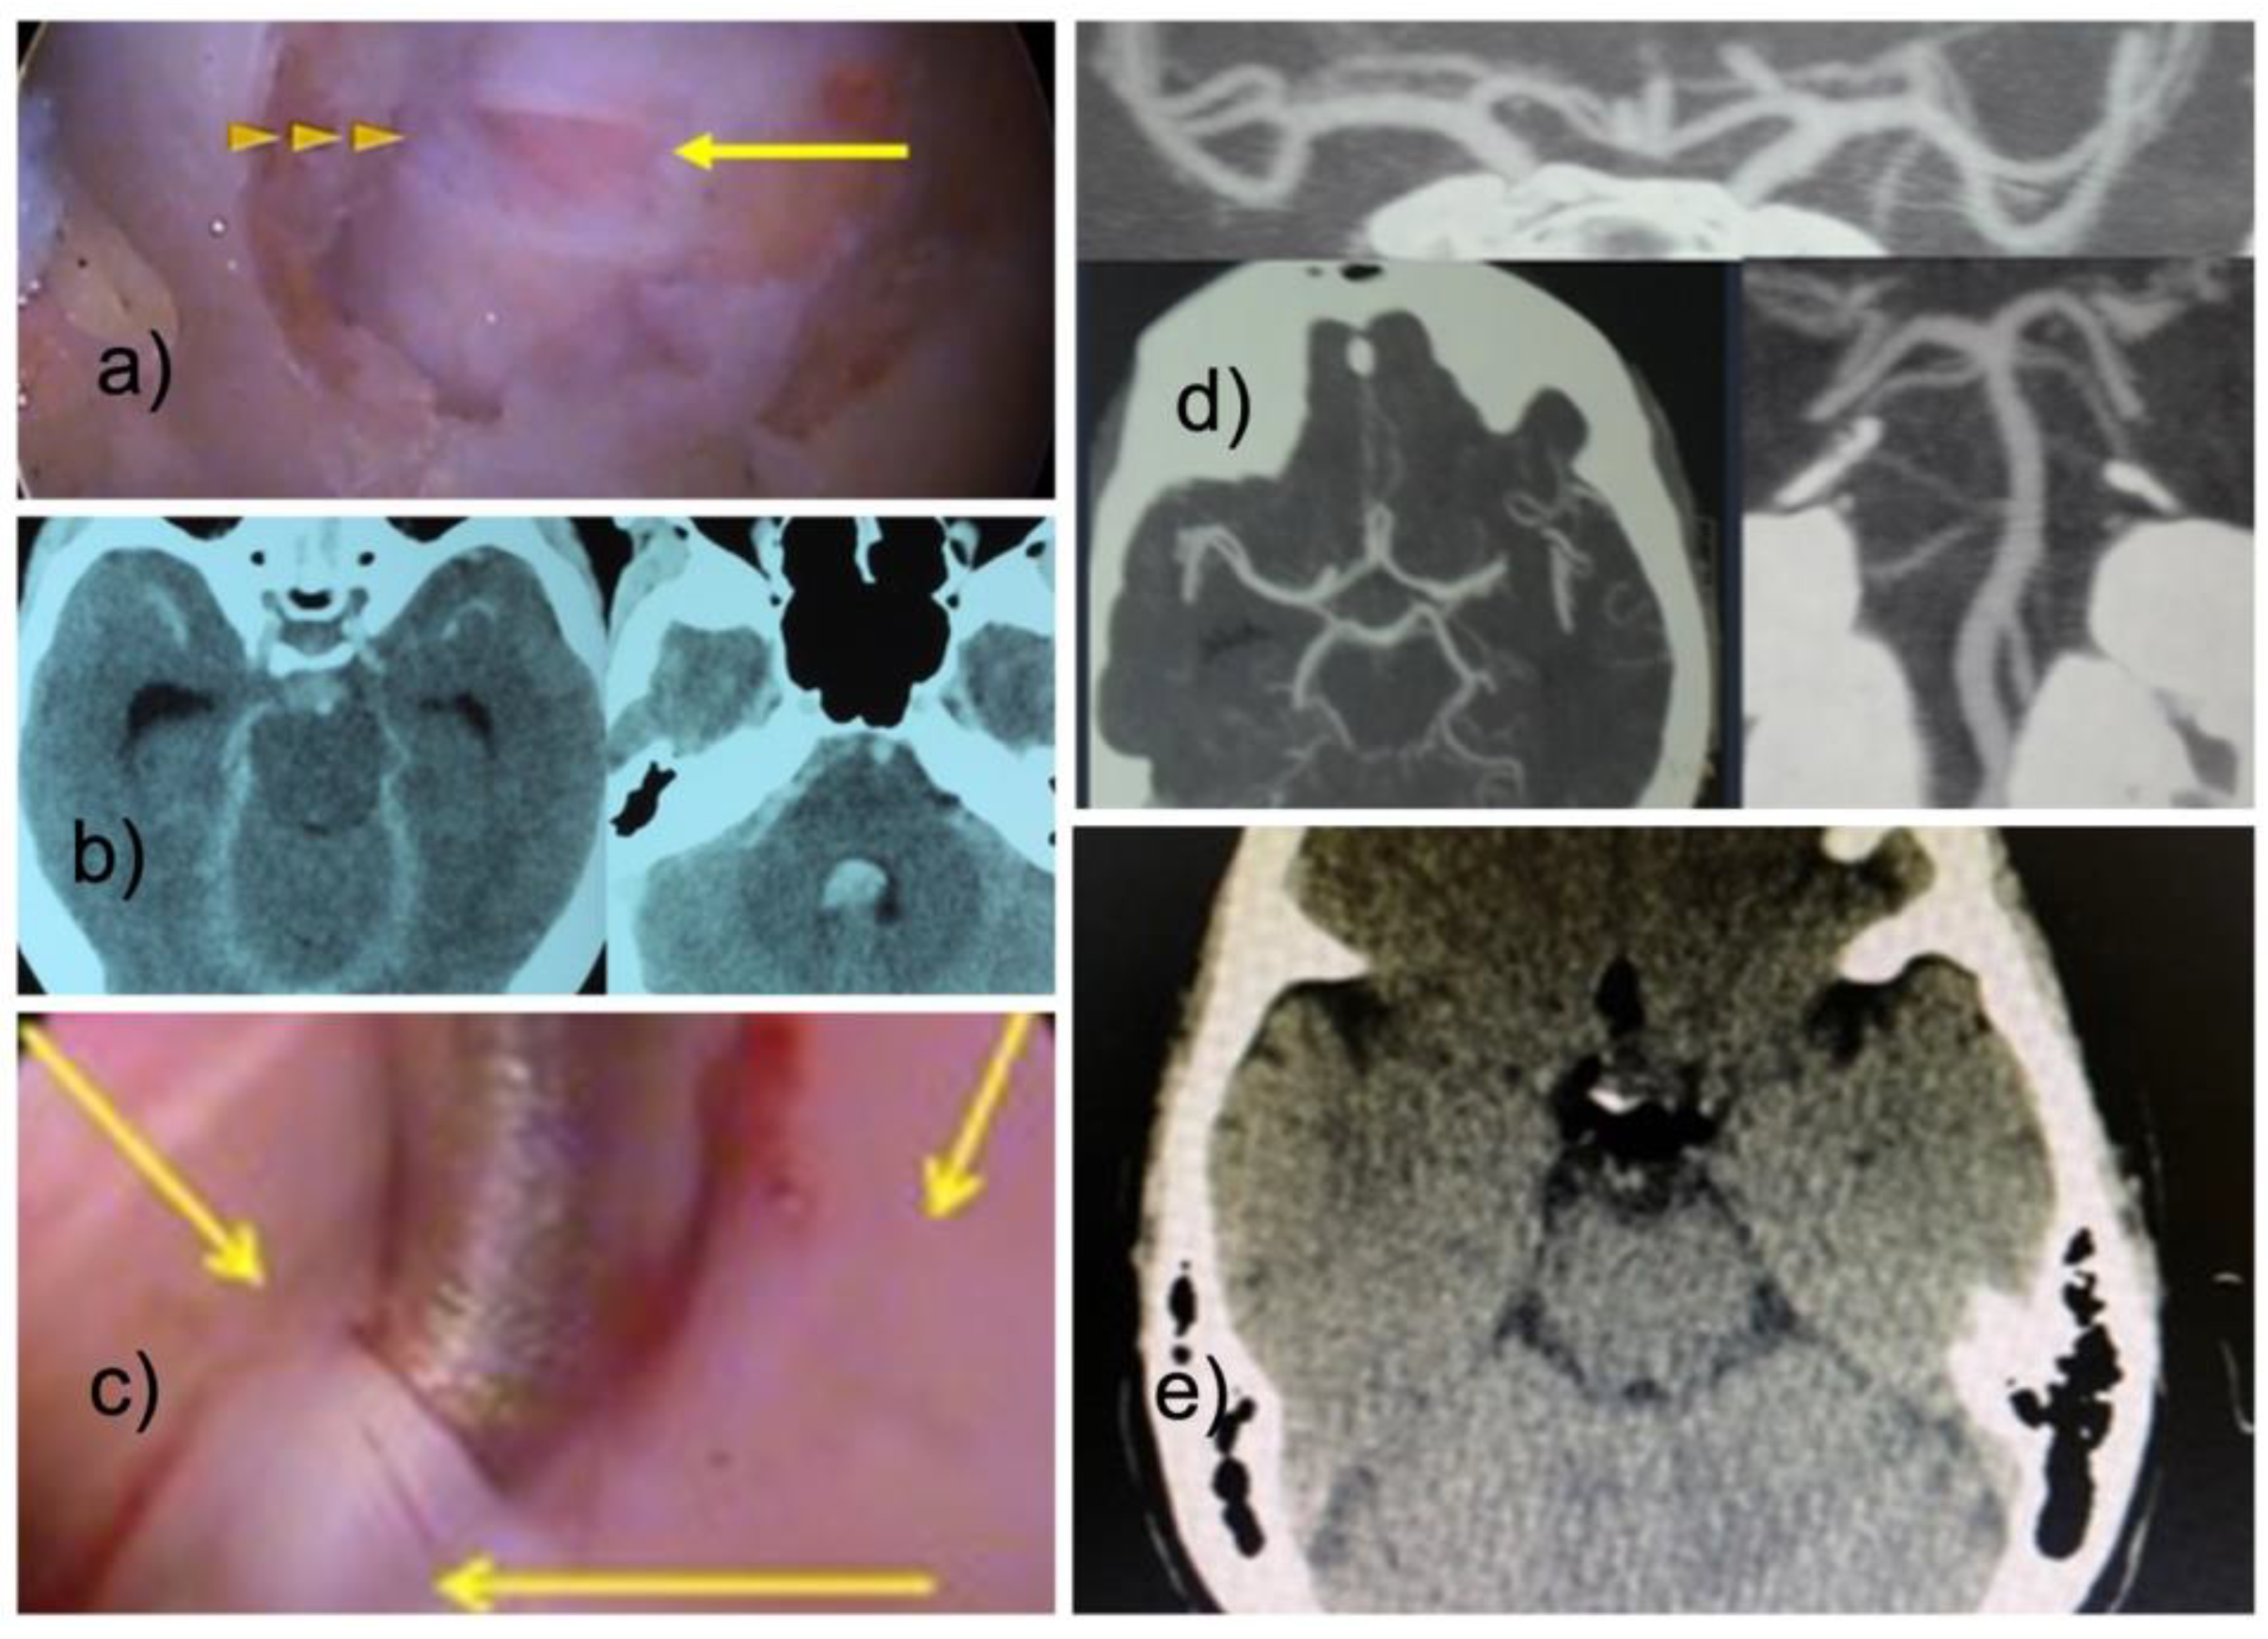

Our series included three patients with seizures who also had a recognized durotomy. One of these three patients had intracranial air on his postoperative brain CT after lumbar endoscopy (Figure 3). Another one suffered from cardiac arrest.

Figure 3.

With the interlaminar endoscopic technique, incidental durotomies are frequently encountered in the posterior dural sac (a). They are associated with the use of power tools but can also occur during the sharp opening of the ligamentum flavum. In this exemplary patient—a 52-year-old female with a C6/7 disc herniation decompressed with the interlaminar technique - fluid entered the intradural space through the small incidental durotomy shown in panel (a). The surgeon had difficulty controlling the epidural bleeding encountered during the otherwise seemingly uneventful operation. He increased the hydrostatic pressure by raising and compressing the fluid bags with a Level I device to improve visualization. Postoperatively, the patient complained of diplopia and headaches. A head CT revealed subarachnoid blood and hydrocephalus typical of Fischer Grade 4 subarachnoid bleeding (b). A durotomy was encountered (c). A postoperative surveillance CT angiogram was normal and did not show any aneurysm or AV-malformations (d). The patient was treated with supportive care measures and recovered fully. The postoperative head CT of another lumbar durotomy patient revealed some free air (e).

The remaining patient of these three developed spinal headaches and diplopia on postoperative day one when her deteriorating neurological function was investigated with a brain computed tomography (CT) scan showing intraventricular hemorrhage consistent with a Fisher Grade IV subarachnoid hemorrhage [34] that did however, ultimately not demonstrate a cerebral aneurysm or AV-malformations after a surveillance CT angiogram was performed at three months postoperatively. The seizures in all three patients were treated medically and the patients were stabilized.